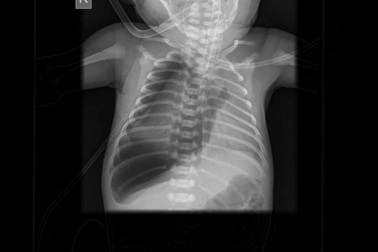

Kén khí to ở phổi bé 1 ngày tuổiSau sinh 1 ngày, con của sản phụ B.T.T đột nhiên suy hô hấp, thở nhanh co lõm lồng ngực và được chuyển từ bệnh viện Từ Dũ sang bệnh viện Nhi đồng 2.

Đây là bệnh rất ít mẹ bầu biết, vì vậy nên chú ý tầm soát để “cứu” con ngay sau sinhSau sinh 1 ngày, bé Nguyễn Đ. D con của sản phụ Nguyễn Thị Đ.H (Vinh Tân, TP. Vinh, Nghệ An) bị tình trạng suy hô hấp, co lõm lồng ngực có biểu hiện tím tái, thở rên nhiều, thể trạng non yếu, suy hô hấp. Được biết trẻ sinh thiếu tháng nặng 2300g, bị vàng da tăng Bilirubin tự do.

Bé gái 2 tuổi viêm phổi hoại tử sau 6 ngày ho, sốtSau 6 ngày xuất hiện các triệu chứng ho và sốt, một bé gái 2 tuổi chuyển biến viêm phổi hoại tử, tổn thương khoảng 1/4 phổi phải. May mắn trẻ được cấp cứu kịp thời tại Bệnh viện Đa khoa Hồng Ngọc và hồi phục sau 15 ngày mà không cần phẫu thuật.